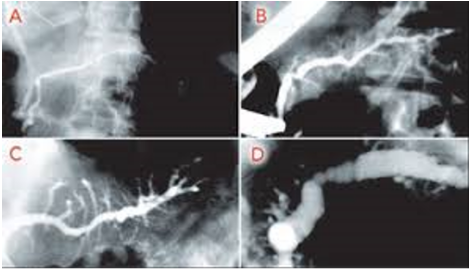

What is seen here?

Dilated pancreatic duct with strictures and abnormal appearance due to CHRONIC PANCREATITIS